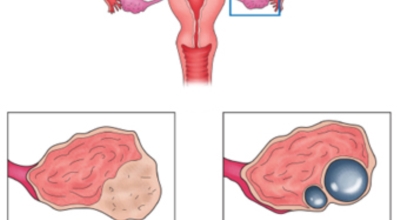

난소낭종이란 난소에 발생되는 물혹이지요. 안에는 그냥 수액이나 장액이지만, 혈액일 수도 있으며, 지방이나 농양일 수도 있어요. 이 난소낭종은 없어졌다 생겼다 하는 기능성 낭종과 점점 커지는 악성 낭종으로 나뉘는데요. 주로 악성 낭종이 문제일 것이라고 생각하지만 기능성 낭종도 커지면 터지면서 사람을 응급실로 실려가게 만들어요.

기능성 낭종 : 배란 낭종이라고도 하며 보통은 증상을 유발하지 않는 가장 흔한 종류의 낭종이지요. 그들은 난포 낭종 ( 난포에서 발생, 난소의 작은 주머니) 및 황체 낭포(난포가 난자를 방출한 후 발생)로 형성될 수 있어요.

유피종 및 기형종 : 태어날 때 부터 존재하며 머리카락, 뼈, 치아 및 피부와 같은 다른 조직을 포함합니다. 여성의 십만 명에 열명 정도가 이러한 유형의 낭종이 있는 것으로 추정되는 비교적 드문 경우이지요 .

낭종: 난소 표면에 형성되며 난소의 체액이나 일부 조직으로 채워져 있어요.

자궁내막증 : 이것은 자궁 외부 조직에서 자자고 혈액으로 가득 찬 낭종이지요.